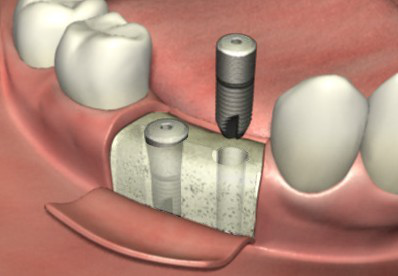

ЁЁЁЁ1ЁЂЪжЪѕЧАвЊЯШзіИіПкЧЛШЋОАЦЌЃЌвдШЗБЃбРВлЙЧЪЪКЯзіжжжВбРЃЌжЎКѓдйгЩвНЩњЩшМЦГіОпЬхЕФжжжВЗНАИЁЃ

ЁЁЁЁ2ЁЂЪжЪѕПЊЪМЃЌЯШдкбРВлЙЧЩЯБИПзВЂжВШыжжжВЬх(ШЫЙЄбРИљ)ЃЌШЛКѓЕШД§3~6ИідТЕФЙЧНсКЯЦкЁЃ